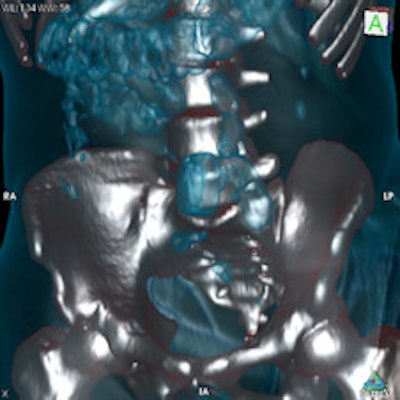

Top left: Axial plane in pulmonary window showing three pellets underneath the tongue. Top right: 3D reconstruction of an incidental finding of three sublingual cocaine pellets in a case of brawl/fist fight with subsequent CT and scan of the viscerocranium. The patient was immediately put under arrest and transferred to the affiliated custody ward. This scan was performed to rule out facial fractures sustained during the fist fight. Bottom left: Secured evidence of similar pellets (weight approximately 1 g). Bottom right: 3D reconstruction of gas-filled condom with two pouches (bags) of cocaine powder inside located in the descending colon. All images courtesy of Dr. Patricia Flach.To determine which diagnostic imaging procedures produce the best results, radiologists from Bern and Zurich compared the accuracy of different modalities in a retrospective study. They evaluated 35 CT exams, 70 digital radiography (DR) exams, and 30 low-dose linear slit digital radiography (LSDR, Lodox Systems) exams taken of 83 suspects between February 2004 and April 2011.